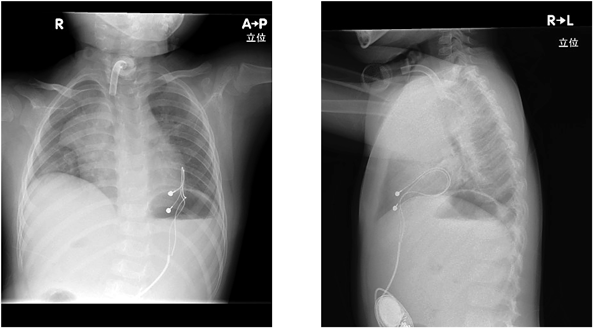

失神を繰り返し,ペースメーカを植え込んだ先天性中枢性低換気症候群の1例Congenital Central Hypoventilation Syndrome with Recurrent Syncope Requiring Pacemaker Implantation: A Case Report